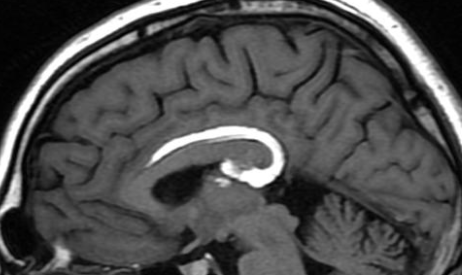

Lipome péricalleux

- Antérieur: tubulonodulaire

- Postérieur: curvilinéaire

- Rechercher des malformations du corps calleux associées